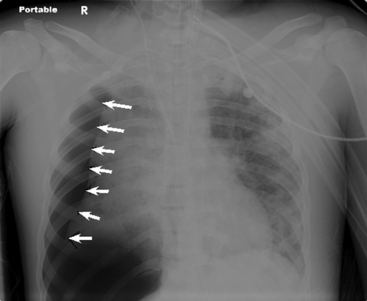

A pneumothorax will produce an air-tissue interface in the pleural cavity because the pneumothorax contains only air with no pulmonary vascular markings, whereas the lung contains air, tissues, and vessels. The presence of a significant pneumothorax will cause partial or complete collapse of the adjacent (ipsilateral) lung. Note that free pleural air will accumulate in the highest portions of the chest so that the location of the air is influenced by the patient’s position when the X-ray is obtained. In an upright film, free pleural air is typically observed above the apex of the lung, whereas in a supine film the air may accumulate along the anterior and lateral aspects of the lung and along the diaphragm (Fig. 10-7).

image

Fig. 10-7 Tension pneumothorax. This film was obtained as part of a routine daily chest radiograph to monitor for endotracheal tube placement in this 18-year-old male with methicillin-resistant Staphylococcus aureus necrotizing fascitis. This is a supine AP film that demonstrates near total atelectasis of the right lung. The pneumothorax is visible along the inferior and lateral aspects of the right chest, with a shift of the cardiac silhouette to the left. There is clear visualization of the lung-air interface (arrows) seen along the lateral and inferior margins of the right lung. This is a tension pneumothorax because the mediastinum is markedly shifted and the right hemidiaphragm is flattened out of the field of view.